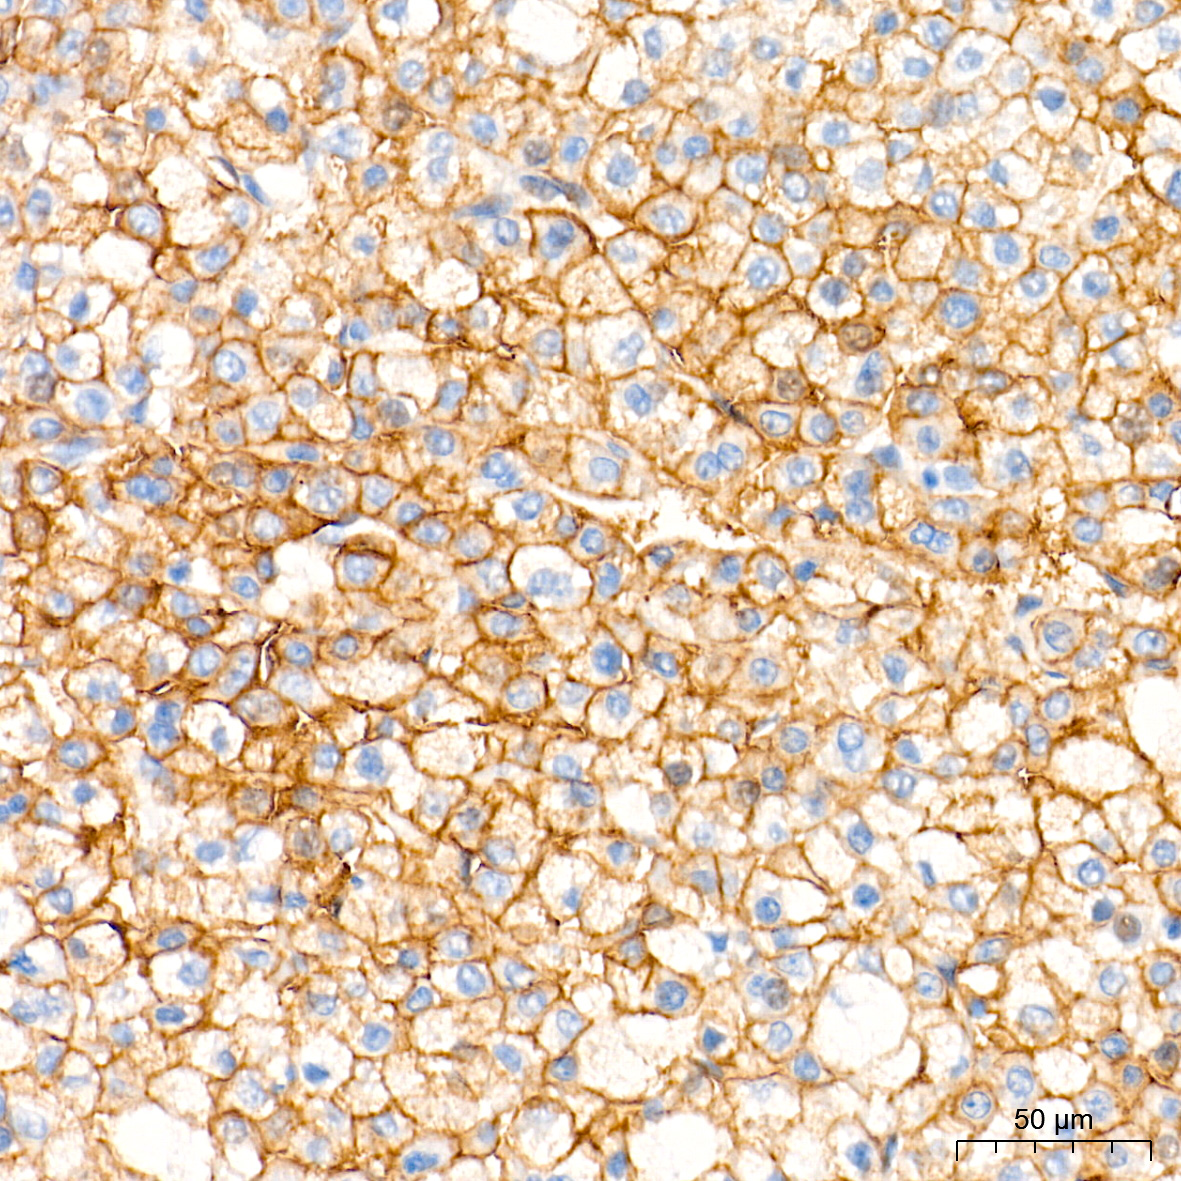

| Immunohistochemistry analysis of paraffin-embedded Human colon carcinoma tissue using [KD Validated] MCT1 Rabbit mAb (A27270) at a dilution of 1:600 (40x lens). High pressure antigen retrieval performed with 0.01M Tris-EDTA Buffer (pH 9.0) prior to IHC staining. |

| Immunohistochemistry analysis of paraffin-embedded Human esophagus tissue using [KD Validated] MCT1 Rabbit mAb (A27270) at a dilution of 1:600 (40x lens). High pressure antigen retrieval performed with 0.01M Tris-EDTA Buffer (pH 9.0) prior to IHC staining. |

| Immunohistochemistry analysis of paraffin-embedded Human liver cancer tissue using [KD Validated] MCT1 Rabbit mAb (A27270) at a dilution of 1:600 (40x lens). High pressure antigen retrieval performed with 0.01M Tris-EDTA Buffer (pH 9.0) prior to IHC staining. |